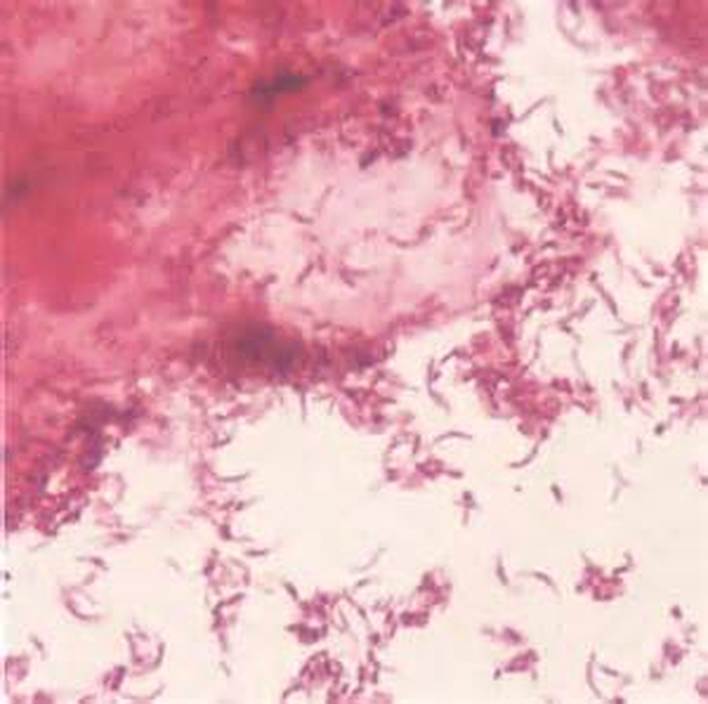

В сети немало фото, на которых можно увидеть, как грибок поражает слизистую интимных органов женщины.

Чтобы поставить правильный диагноз в случае молочницы у детей, необходимо взять мазок выделений из пораженной области (влагалище или ротовая полость). Врач наносит содержимое выделений на предметное стекло, просушивает, окрашивает специальным образом и осматривает в микроскоп. Диагноз подтверждается при наличии колоний грибков в поле зрения. Лечить кандидоз самостоятельно нельзя — это может привести к хронической инфекции.